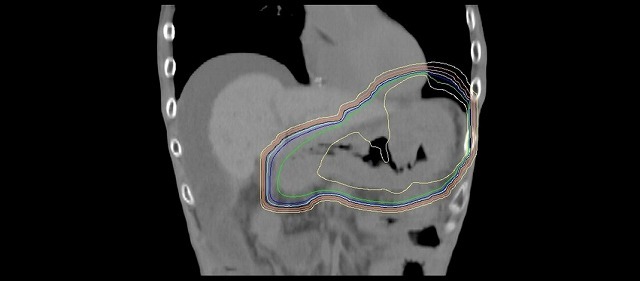

手術で取り残す可能性が高い箇所を中心にIMRTで照射。

胃や小腸、腎臓など周囲の臓器を避けて照射している。